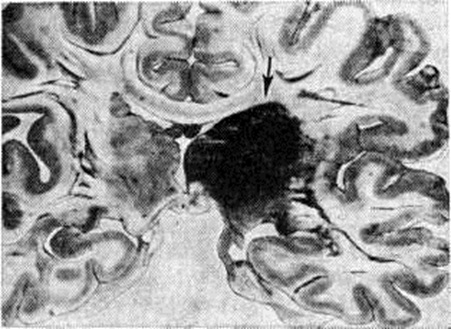

Кровоизлияния типа геморрагического пропитывания возникают преимущественно в зрительных буграх, реже в мосту мозга и составляют 15% внутримозговых кровоизлияний. Они являются результатом слияния мелких очагов кровоизлияний, возникающих путём диапедеза из мелких сосудов, имеют вид очагов красного цвета, дряблой консистенции и в силу внешнего сходства иногда напоминают геморрагический инфаркт. В первые часы Инсульт нарушается проницаемость сосудов на границе с кровоизлиянием, развивается отёк; кровь распространяется по ходу нервных волокон. К концу первых суток наблюдаются лейкостазы и лейкодиапедез, размеры очага увеличиваются за счёт диапедезных геморрагий и некробиотических изменений в отёчном веществе мозга. Через двое суток начинается процесс репарации — появление зернистых шаров и гипертрофированных астроцитов; позже образуется вал из астроглии и новообразованных сосудов, кровь подвергается гемолизу, появляются макрофаги с гемосидерином, образуются аргирофильные и коллагеновые волокна. Исходом кровоизлияния может быть формирование глиомезодермального рубца или кисты, содержащих гемосидерин (рисунок 9). В 80—85% кровоизлияний на вскрытии выявляется прорыв крови в желудочки, значительно реже — в подпаутинное пространство. В последнее кровь может также проникнуть из четвёртого желудочка. Первичные вентрикулярные геморрагии нетравматического генеза — явление казуистическое. При разрыве врождённых аневризм артерий основания мозга возникают первичные субарахноидальные кровоизлияния, которые обычно локализуются на базальной поверхности или в латеральной борозде; иногда кровь проникает в субдуральное пространство; часто повреждается вещество мозга (субарахноидально-паренхиматозные кровоизлияния). Расположение гематом, образующихся при этом, зависит от локализации аневризмы, обычно это базальный отдел лобной доли или височная область. В части случаев при незначительном субарахноидально-паренхиматозном кровоизлиянии возможен массивный прорыв крови в желудочки (рисунок 10), что иногда ошибочно диагностируется как первичное вентрикулярное кровоизлияние.

Рис. 10.

Фронтальный срез головного мозга на уровне передние рогов боковых желудочков при разрыве аневризмы передней соединительной артерии; заполненные кровью желудочки (указано стрелкой).